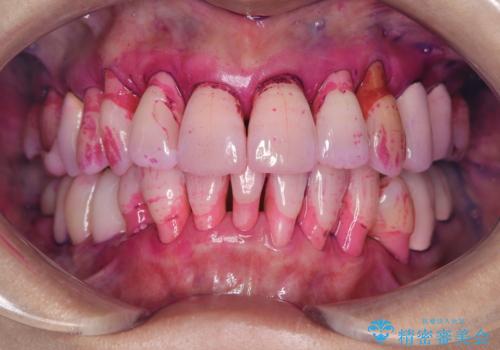

- 歯のホワイトニングを希望されて来院された患者様です。

レーザーを用いたホワイトニングを行いました。

施術前後の変化に大変満足されていました。

薬剤を塗布し、レーザー照射を3セット行いました。